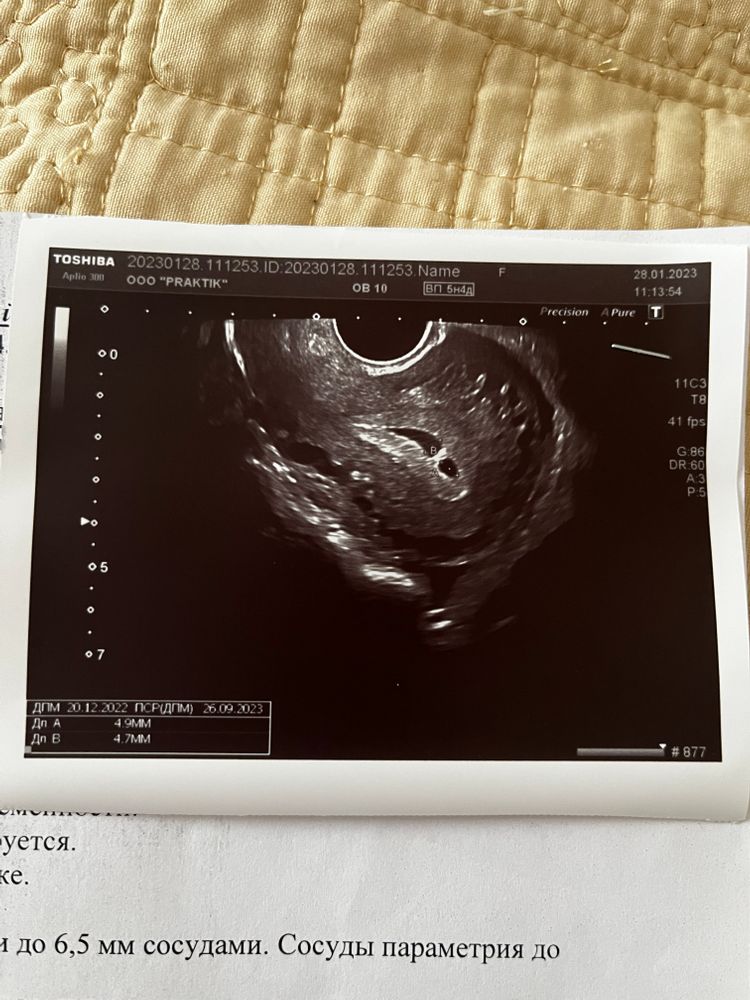

Между маткой и хорионом определяется анэхогенный участок неправильно-овойдной формы размером 11х6 мм.

лечение дюфастон, спокойствие и покой половой. Выделений никаких не было. Гематома вышла на неделе 19 в итоге, все хорошо дальше.